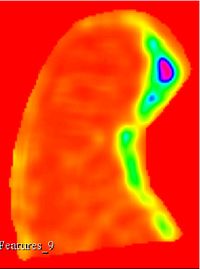

This extensions contain several modules that can be used to compute feature maps of N-Dimensional images using two well-known texture analysis methods: the study of Grey Level Co-occurrence Matrix (GLCM) and the study of Grey Level Run Length Matrix (GLRLM). The main algorithms used in this extension are part of a remote module of ITK called itkTextureFeatures Key Features:

Texture features

Texture feature maps

Run Length texture feature maps